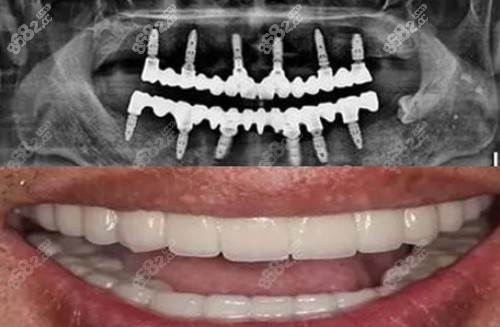

在常德地区,牙齿缺失问题困扰着不少人,而种植牙成为了修复牙齿的理想选择。常德好大夫口腔医院在种植牙领域声名远扬,其背后的种植牙医生团队更是功不可没。这些种牙高手凭借着的实力与独特技艺,为众多患者解决了牙齿缺失的难题。他们究竟有着怎样的背景?又掌握了哪些独特的种牙技艺呢?接下来,就让我们深入了解常德好大夫口腔医院的种植牙医生,揭秘他们的实力与独特技艺。

的技术掌握:随着口腔医学的不断发展,种植牙技术也在不断更新换代。常德好大夫口腔医院的种植牙医生们紧跟时代步伐,积极学习和掌握的种植牙技术。例如,他们熟练掌握了数字化种植技术,通过口腔 CT 扫描、计算机辅助设计和制造等手段,能够规划种植体的位置、角度和深度,大大提高了种植手术的性和。此外,他们还掌握了即刻种植、即刻负重等技术,能够为患者缩短治疗周期,减少痛苦。

美学修复技艺:种植牙不仅要牙齿的功能,还要注重美观。常德好大夫口腔医院的种植牙医生们具备出色的美学修复技艺,他们能够根据患者的面部特征、肤色、邻牙形态等因素,设计出与自然牙齿相似的牙冠,使种植牙在外观上与周围牙齿融合。在选择牙冠材料时,医生会充分考虑其美观性、耐磨性和生物相容性,为患者提供高品质的美学修复。